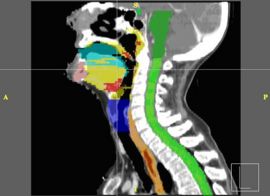

Interactive Segmentation

Modern radiotherapy requires manual contouring of both target structures and healthy normal tissues, to ensure adequate coverage with minimal radiation side effects. The goal of this project is to evaluate if 3d-slicer is capable of providing a comfortable user interface needed for physicians and physicists to perform manual contouring.

We currently use commercial tools for segmentation. The approach will be to import the best ideas from existing systems, but also include tools which are missing such as tilted-plane drawing tools and intelligent contour interpolation.